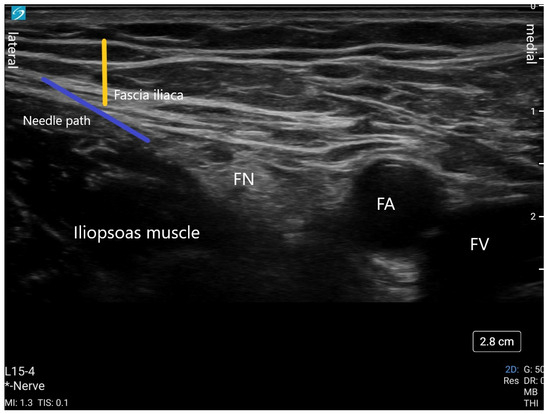

3.2. Femoral Nerve Block

The femoral nerve block (FNB) continues to be one of the mainstays of regional techniques for pain management after hip fracture. Its ease of performance lends itself to accessible mastery and applicability. The femoral nerve supplies sensory fibers to the hip joint in addition to motor and sensory supply to the thigh. It arises from lumbar spinal roots L2-L4. The nerve is commonly blocked posterior to the inguinal ligament where it lies lateral to the femoral artery. An FNB is often conducted with ultrasound guidance using a high-frequency linear probe at the femoral crease with the patient lying supine. A lateral approach using an in-plane needle technique is used to inject local anesthetic (15–20 mL) either above or below the nerve (Figure 4). A continuous nerve catheter can also be placed using ultrasound guidance for prolonged analgesia.

Figure 4. This is an ultrasound image of a femoral nerve block. The yellow line indicates the fascia iliaca plane. The blue line represents the needle trajectory. Local anesthetic is deposited below the nerve and above the nerve. FN (femoral nerve); FA (femoral artery); FV (femoral vein); * Nerve (ultrasound setting is in Nerve mode).